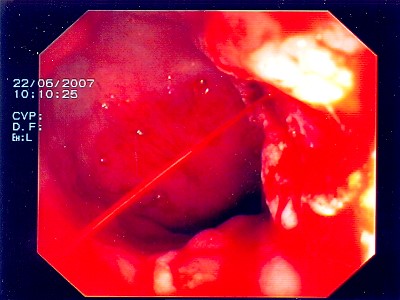

Sichere Blutstillung durch einen Metallclip